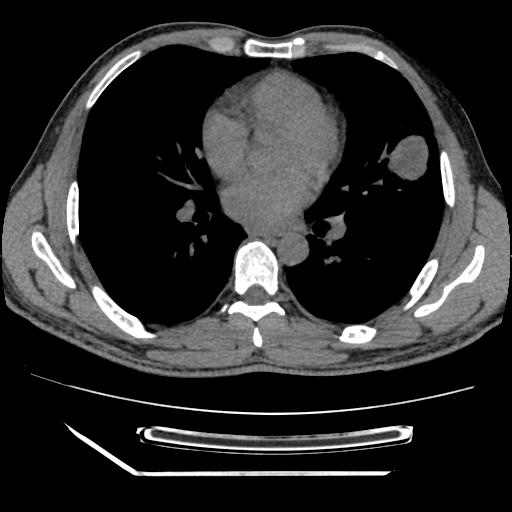

男,38岁,于2009年8月9日晚突发左侧胸痛,今x线提示左下肺阴影,为了明显确诊断,行ct检查,

纵膈窗

左肺舌叶病变。主体病灶呈类圆形中心密度低,成液化趋势周边班片影分布

考虑肺脓肿

虽然实验室检查支持炎性病变,且病变内有坏死改变(中央呈大片状低密度影),但仍不能掉以轻心,鳞癌也可以有这种影像改变。